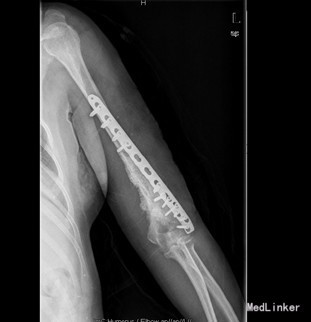

患者女,39岁,因“左肱骨骨折术后左肩关节左肘关节活动障碍6月”入院。 6月前患者外伤致左肱骨中下段粉碎性骨折,患者到当地人民医院行左肱骨骨折髓内钉及切开钢丝捆扎固定手术治疗(具体手术方式不详)。术后手术伤口恢复可,但患者左肩关节活动明显受限,并左肱骨下份肿胀严重,左肘关节活动稍受限。现患者左肩关节及左肘关节活动无明显好转,左上臂下段肿胀,皮温高。今患者到我院求进一步治疗。

查体:左上肢肱骨下段内侧有一10cm手术疤痕,下段肿胀,皮肤无明显发红。余四肢未见异常,活动无受限;左肱骨下份肿胀,未触及局限包块及波动感,肿胀区皮温高。桡动脉搏动正常。左肩关节活动明显受限,外展约20度,前伸后屈约20度,内外旋约15度,肘关节伸0度、屈45度。余关节活动无异常。 辅查:X片示左肱骨中下段骨折术后,内固定在位。

初步诊断:1、左肱骨骨折术后骨不愈合。2、左肩、左肘关节活动障碍 诊疗计划:择期行左肱骨髓内钉取出术、左肱骨骨折钢板螺钉内固定术,人工骨植骨。

术中见肱骨下份原骨折处软组织肿胀,瘢痕形成较多,有少量骨痂生成,能见原骨折端。取出髓内钉及固定钢丝后,骨折明显不稳定有假关节活动。未见明显炎性增生、渗出及坏死组织。并取随内及骨折周围部分组织送病检及培养。